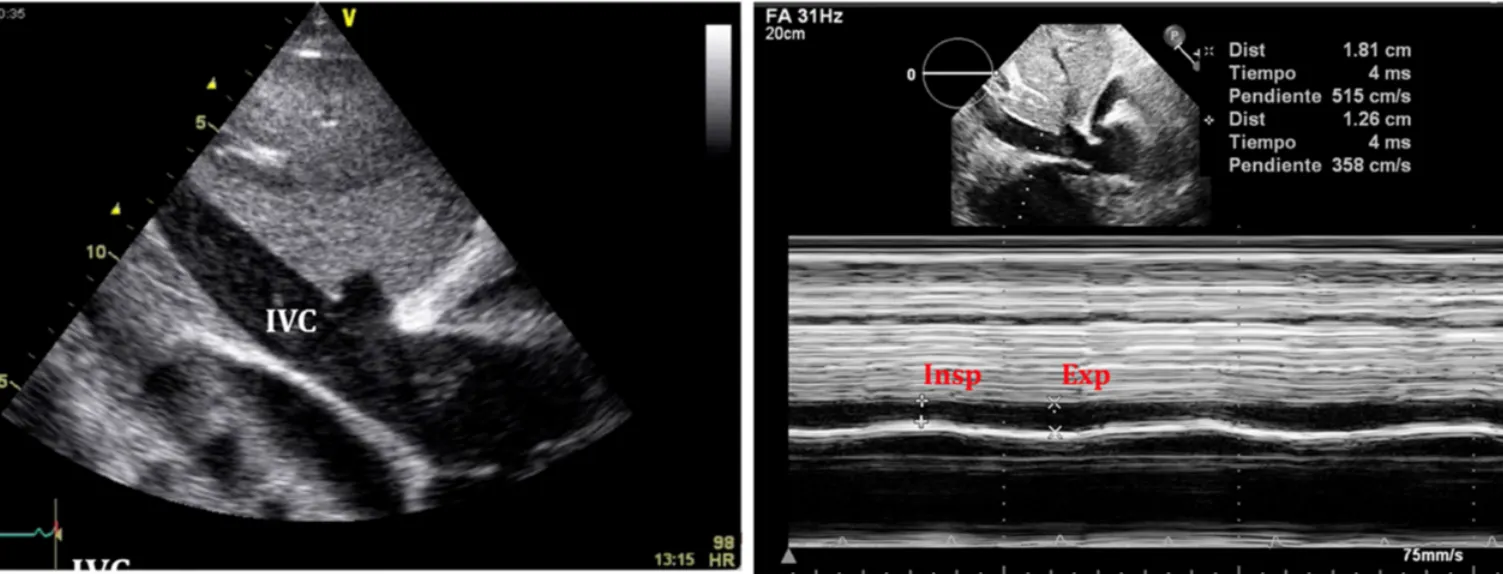

A4. IVC plethora (most sensitive)

•

Inspiration 시 IVC volume 이 감소가 일어나는 것이 일반적

IVC plethora 는 diameter 2cm 이상 에서 최대 직경이 50% 미만 감소 시를 말하는 것.

주의해야하는 건 trauma같은 hypovolemia의 경우는 안 나타나는 경우도 있음.